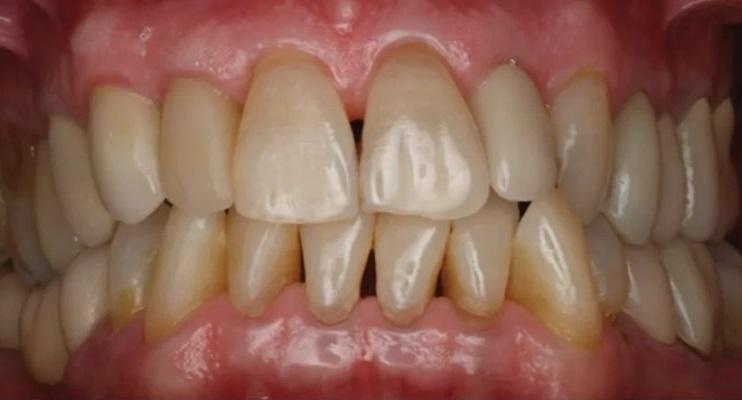

На контрольном осмотре через 16 месяцев клиническая оценка выявила сохраненный объем гребня и стабильную кератинизированную мягкую ткань (Фото 22 и Фото 23). Рентгенологический анализ подтвердил стабильный уровень кости вокруг имплантата № 2.4 и положительные рентгенологические изменения, свидетельствующие о регенерации тканей на медиальной поверхности зуба № 2.5, включая восстановление периодонтальной связки (Фото 24).

Фото 22 и Фото 23. На контрольном осмотре через 16 месяцев: интраоральный окклюзионный вид (Фото 22) и латеральный вестибулярный вид (Фото 23) демонстрируют реставрацию на имплантате с винтовой фиксацией.